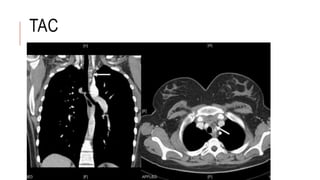

TAC